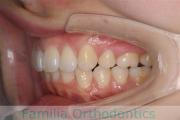

No.22V-409

- 叢生

- 16歳

- 女性

- 44

- 8|58

- FEA

- 86万円

八重歯を治したいということで来院されました。下あごの左ずれのある上顎前突(出っ歯)・叢生(でこぼこ)でしたので、上は左右から、下はで左のみ小臼歯を抜歯して、歯科矯正用アンカースクリューとマルチブラケット法にて治療を行いました。2年強、30回程度の通院が必要でした。

上下とも前歯の叢生(でこぼこ、凹凸、ガタガタ)があるため、保定を怠ると後戻りのリスクがあります。